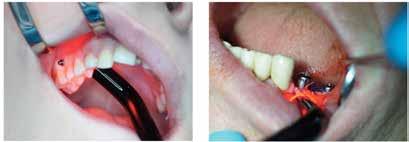

Influence of red laser light (635nm) on dental implants stability

Many studies have revealed that the LLLT (photobiomodulation) is a non-invasive therapy that can take part in the proliferation of fibroblasts and osteoblasts and, therefore, in bone healing, as well as increasing peri-implant bone density.[3–6] In our recent study, we assessed the effects of photobiomodulation (LLLT) on implant stability and bone density after peri-implant irradiation with a 635-mm diode laser (SmartM PRO, Lasotronix, Poland) at an energy dose of 4J (8J/cm2) using Periotest device and CBCT analysis. The main finding of the clinical study was that the implants

Fig.1 Photobiomodulation at mini-implant site.

Fig.2 Photobiomodulation at regular implant site.

irradiated with a 635-nm diode laser accounted for significantly higher secondary stability (after four weeks) and bone density (after 12 weeks) in contrast to non-irradiated implants/sites.[6] Furthermore, in another randomized clinical trial, we analyzed the effect of a 635-nm diode laser on the stability of orthodontic microscrews. We obtained significantly higher secondary stability (after 30 and 60 days) in comparison to the non-irradiated implants.[5] In conclusion, the recent studies showed the diode laser at a wavelength of 635-nm enhances the secondary stability of regular implants and orthodontic micro-screws and peri-implant bone density.